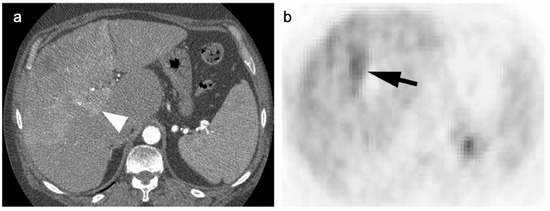

4. Hepatocellular Carcinoma